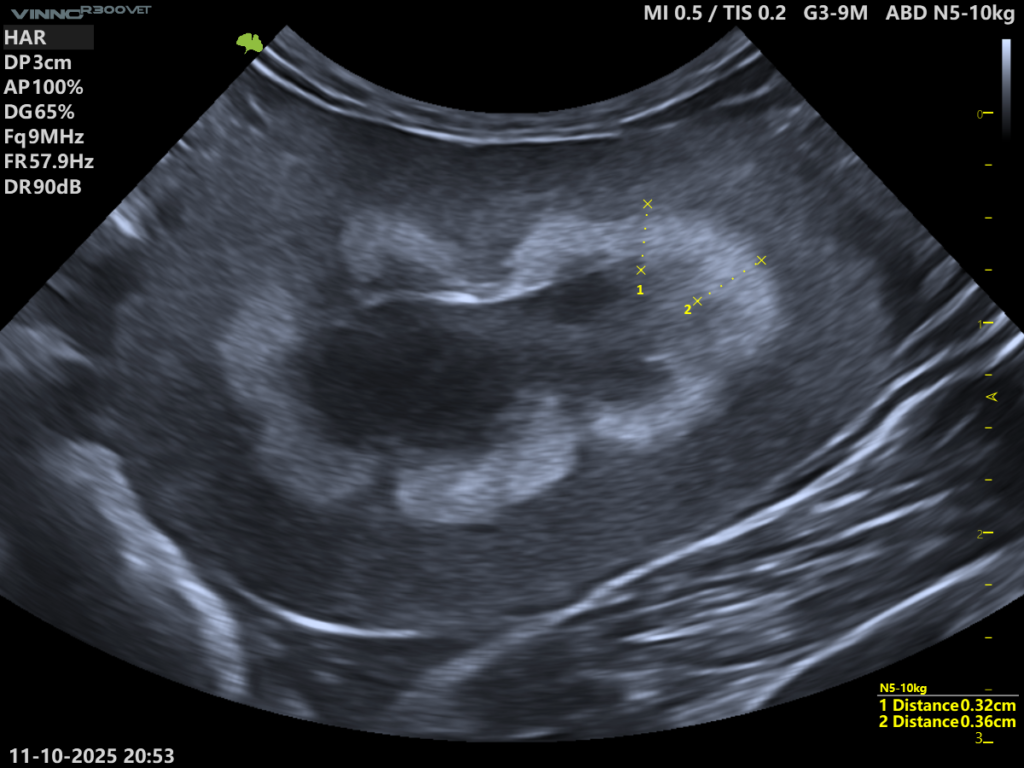

W pracy Cordella i wsp. zaproponowano dodatkowe kryterium pomocne w różnicowaniu obu postaci MRS. Zmiany o większej grubości (około ≥ 2,5 mm) częściej odpowiadały obrazowi MRS-band (MBS), natomiast cieńsze struktury klasyfikowano jako MRS-line.

Należy podkreślić, że wartość ta ma charakter orientacyjny i nie stanowi sztywnego kryterium diagnostycznego. Może jednak być użytecznym elementem praktycznym w codziennej pracy ultrasonograficznej.